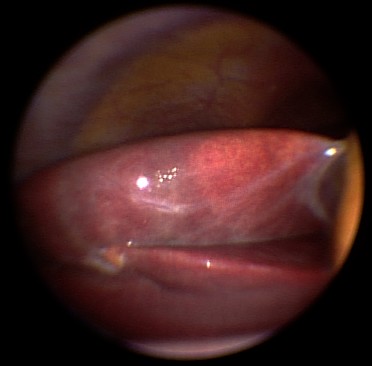

Fokale Mehrverfettung